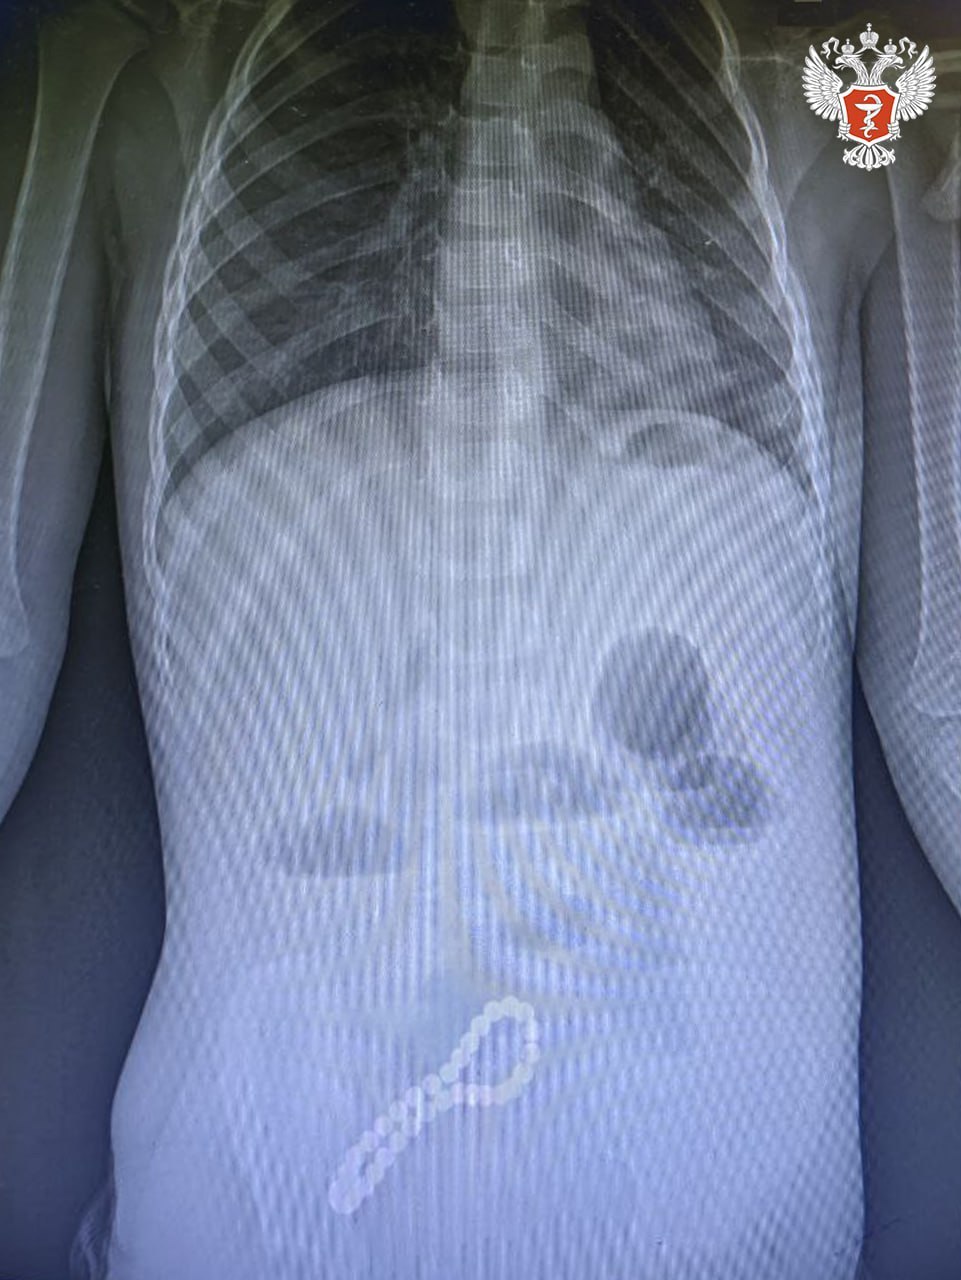

Хирурги выявили нарушение функций работы кишечника. При помощи рентгенограммы врачи поставили диагноз — инородное тело в кишечнике и приняли решение о его удалении.

— Было принято решение об операции. Мы провели минилапаротомию и увидели, что магнитами, которые притянулись друг к другу, соединены петли кишки в ее стенке отверстия. В ходе операции удалили все 30 магнитных бусин: 29 маленьких и одну большую.